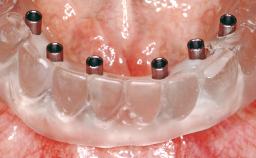

Conventional Loading of Eight Implants in the Maxilla and Final Restoration with a Full-Arch Gold-Ceramic FDP

# of Implants 8

Type of Implants One-Piece

Prosthesis Type FDP